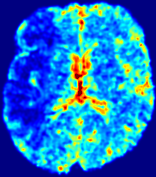

LesionRefer to captionRefer to captionRefer to captionRefer to captionRefer to captionRefer to caption𝐕rgbsubscript𝐕𝑟𝑔𝑏{\bf{V}}_{rgb}Refer to captionRefer to captionRefer to captionRefer to captionRefer to captionRefer to caption𝐕2subscriptnorm𝐕2{\|\bf{V}}\|_{2}Refer to captionRefer to captionRefer to captionRefer to captionRefer to captionRefer to captionRefer to caption3.53.53.52.82.82.82.12.12.11.41.41.40.70.70.70.00.00.0(mm/s)𝑚𝑚𝑠(mm/s)D𝐷DRefer to captionRefer to captionRefer to captionRefer to captionRefer to captionRefer to captionRefer to caption0.0200.0200.0200.0160.0160.0160.0120.0120.0120.0080.0080.0080.0040.0040.0040.0000.0000.000(mm2/s)𝑚superscript𝑚2𝑠(mm^{2}/s)Slice #1Slice #2Slice #3Slice #4Slice #5Slice #6

Figure 3: PIANO feature maps for one stroke patient, where the lesion is located in the left hemisphere. Top row: segmented stroke lesion region (white) on different slices, obtained from ISLES 2017. The corresponding slices for the PIANO feature maps are shown in the following rows.

For a better insight into an estimated velocity field 𝐕𝐕{\bf{V}} and diffusion field 𝐃𝐃{\bf{D}}, we compute the following maps: (1) 𝐕rgbsubscript𝐕𝑟𝑔𝑏{\bf{V}}_{rgb}: Color-coded orientation map of 𝐕=(Vx,Vy,Vz)T𝐕superscriptsuperscript𝑉𝑥superscript𝑉𝑦superscript𝑉𝑧𝑇{\bf{V}}=(V^{x},V^{y},V^{z})^{T}, obtained by normalizing 𝐕𝐕{\bf{V}} to unit length and mapping its 3 components to red, green, blue respectively; (2) 𝐕2subscriptnorm𝐕2\|{\bf{V}}\|_{2}: 222 norm of 𝐕𝐕{\bf{V}}; (3) D𝐷D: scalar field in Eq. 5.

Fig. 3 and Fig. 4 show the PIANO feature maps estimated from two ISLES 2017 patients: all are highly consistent with the lesion in both cases. Details of the blood flow trajectories are revealed in 𝐕rgbsubscript𝐕𝑟𝑔𝑏{\bf{V}}_{rgb} by the ridged patterns and the sharp changes of colors in the unaffected (right) hemisphere, while the flat patterns appearing within the lesion provide little directional information about the velocity and indicate low velocity magnitudes. Velocity magnitudes are more directly visualized via 𝐕2subscriptnorm𝐕2\|{\bf{V}}\|_{2}, from which one can easily locate the lesion where 𝐕2subscriptnorm𝐕2\|{\bf{V}}\|_{2} is low. D𝐷D also indicates lower diffusion values in the lesion, though with less contrast potentially due to the fact that it captures the accumulated effect of CA diffusion at the voxel-level.